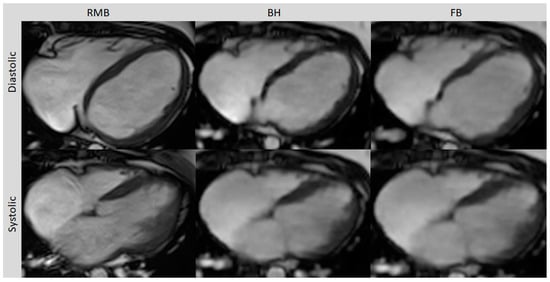

Figure 1.

Axial slices of all three cine sequences in systolic and diastolic phases. FB and BH images are almost equivalent to RMB in the delineating blood–myocardium boundary but with typically a slightly blurrier aspect. Retrospective segmented multi-breath hold (RMB), real-time single/double breath hold (BH), real-time free breathing (FB).

Comparing all three methods, the best image quality was provided by RMB (4.5; range 2 to 5) compared to BH (3.9; range 3 to 5; p = 0.04) and FB (3.6; range 3 to 5; p < 0.01). The image quality with BH was slightly better than with FB but the difference did not reach statistical significance (p = 0.07). The diagnostic confidence was comparable between RMB and BH (p = 0.65) and between RMB and FB (p = 0.84). With RMB, 90% of the cases were rated with high, 5% with intermediate, and 5% with low confidence, whereas with CS-BH and CS-FB, 80% and 75% were rated with high confidence, respectively, and 20% and 25% with intermediate confidence, respectively. Poor image quality with RMB was due to artifacts caused by arrhythmia, whereas BH and FB delivered diagnostic-level image quality in this case (Table 2). Representative images from RMB, BH, and FB are shown In Figure 1 and Figure 2.